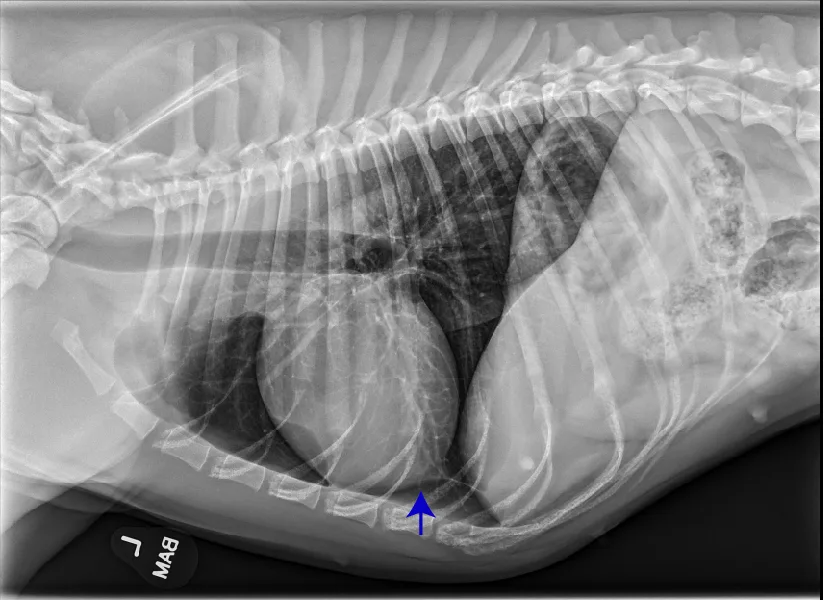

At least 2 orthogonal views, ideally taken during peak inspiration, are necessary for appropriate radiographic study of the cardiovascular system; however, a 3-view study is ideal for comprehensive evaluation of the thorax. Some differences should be considered when deciding to acquire a right versus left lateral projection and a dorsoventral (DV) versus ventrodorsal (VD) projection. On the left lateral view, the cardiac silhouette is typically more rounded and the apex is further elevated from the sternum than in the right lateral view (Figure 1). In the DV view, the cardiac silhouette is commonly displaced cranially and to the left by the diaphragm and appears more rounded than in the VD view. The caudal pulmonary vasculature is better delineated in the DV view, whereas the lung field (particularly the accessory lobe) is better evaluated in the VD view (Figure 2).

FIGURE 1 Normal right and left lateral projections of the thorax in a large, crossbreed dog. The difference in the cardiac silhouette and the apex elevation (arrow) from the sternum in the left lateral view can be seen. VHS, VLAS, modified VLAS (M-VLAS), and VRHi collected from the right lateral view are 10.6, 1.7, 2.8, and 3, respectively, and 10.6, 1.5, 2.9, and 3.4, respectively, collected from the left lateral view. Given these differences, serial radiography should be performed using the same lateral view if only one view is used. In some dogs, roundness of the cardiac silhouette in the left lateral view can be pronounced and misinterpreted as right-sided heart enlargement, particularly if compared with a prior right lateral view. Images courtesy of Federico Villaplana Grosso, DACVR, DECVR